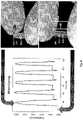

FIG.6 shows the resistance response of a wrinkled metal film strain gauge. Resistance peaks correspond with maximum strain of 5%. The bottom arrow indicates the initial, unstrained resistance of the wrinkled metal film strain gauge.

FIG.7 shows strain cycling of a second embodiment of a wrinkled metal film strain gauge. Panels (A) and (B) show semi-static linear strain cycling. Panel (C) is a top down scanning electron micrograph (SEM) of adjacent wrinkles in contact.